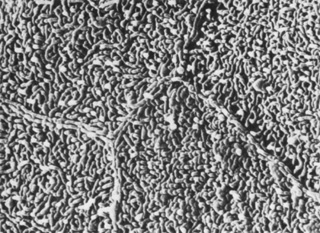

The corneal epithelium is the anterior-most cell layer of the cornea (Fig. 1). It is typically several cell layers thick, consisting of the apical cell squamous layer, the multilayered, polygonal-shaped wing cells beneath the apical layer, and the posterior-most layer of basal cells (Fig. 2). The wing cell layer is two or three cells thick in the central cornea, but tends to be four to five cells thick in the periphery. In total, the epithelium is approximately 50 μm thick in the central human cornea. The epithelium is in a constant state of turnover, with exfoliating apical cells being replaced by underlying wing cells. During normal exfoliation, desquamating cells are released only after the replacement cell has established new tight junctions with neighboring cells and the new apical membrane is capable of maintaining continuity of the tear film.9 Studies of induced exfoliation of a monolayer of epithelial cells with a biologic detergent indicate recovery of the paracellular barriers and transepithelial electric resistance in approximately 1 hour.10 The epithelium completely turns over in approximately 7 days.11 Once injured, a high degree of motility ensures coverage of a denuded area by adjacent basal cells, followed by replacement of the normal complement of cell layers. Basal cells are the only epithelial cells capable of mitosis; however, many epithelial cells originate as the progeny of limbal stem cells and migrate centripetally to supplement or replace cells lost through normal desquamation or injury.12–14 Using immunohistochemical staining for antibodies to keratins, Wiley and associates found regional heterogeneity indicating that the superior corneal periphery and limbus have the greatest numbers of stem cells producing replacement epithelial cells.15 Limbal stem cell deficiency may result in conjunctival epithelium invasion of the cornea, leading to vascularization, the appearance of goblet cells, and an irregular or unstable epithelium that reduces visual acuity and may produce pain or discomfort.16 The epithelium is known to chemically interact with keratocyte cells of the stroma. These interactions appear to be dominated by cytokines such as interleukin-1 (IL-1) and soluble Fas ligand that are released by injured epithelial cells. It would appear that IL-1 is a master regulator for corneal wound healing given its effect on keratocyte apoptosis and the modulation of matrix metalloproteinase and growth factors such as keratinocyte growth factor (KGF) and hepatocyte growth factor (HGF). The Fas ligand system is known to influence the immune privileged state of the cornea. In addition to the epithelial-to-keratocyte communication, keratocytes influence the state of the epithelium via HGF and KGF, which affect cell turnover, motility, and proliferation.17 APICAL CELLS Apical surface cells appear broad and flattened: 4 to 5 μm thick and 40 to 50 μm in diameter. Freshly emerged surface cells appear bright during specular microscopy and have relatively small numbers of microvilli covering their apical membrane (Fig. 3).18

As the cell matures, its specular microscopic appearance tends to darken (Fig. 4). This may be due to changes in surface texture, because microvilli densely cover the apical membrane at this stage of development.4,19 Prior to cell exfoliation, apical surface margins tend to appear smooth, with microplicae clustered only near the center. In its final stages the biomicroscopic appearance of the cell surface appears darker than in its earlier stages (Fig. 5).